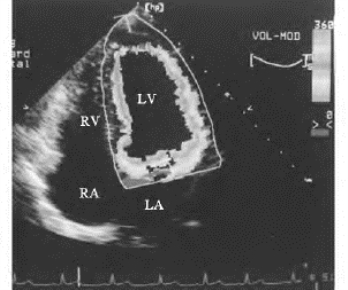

传统的M型超声心动图只能显示右室前壁、室间隔和左室后壁的运动曲线,而无法获得左室侧壁、后室间隔等部位的运动曲线。应用计算机技术在二维超声心室成像的基础上转换,可以获得多方位取样线扫描的运动曲线,称为全方位M型,或解剖M型,进行室壁各方向的向心运动幅度和速度的检测(图19-3)。

图19-3 正常人室壁运动M型曲线